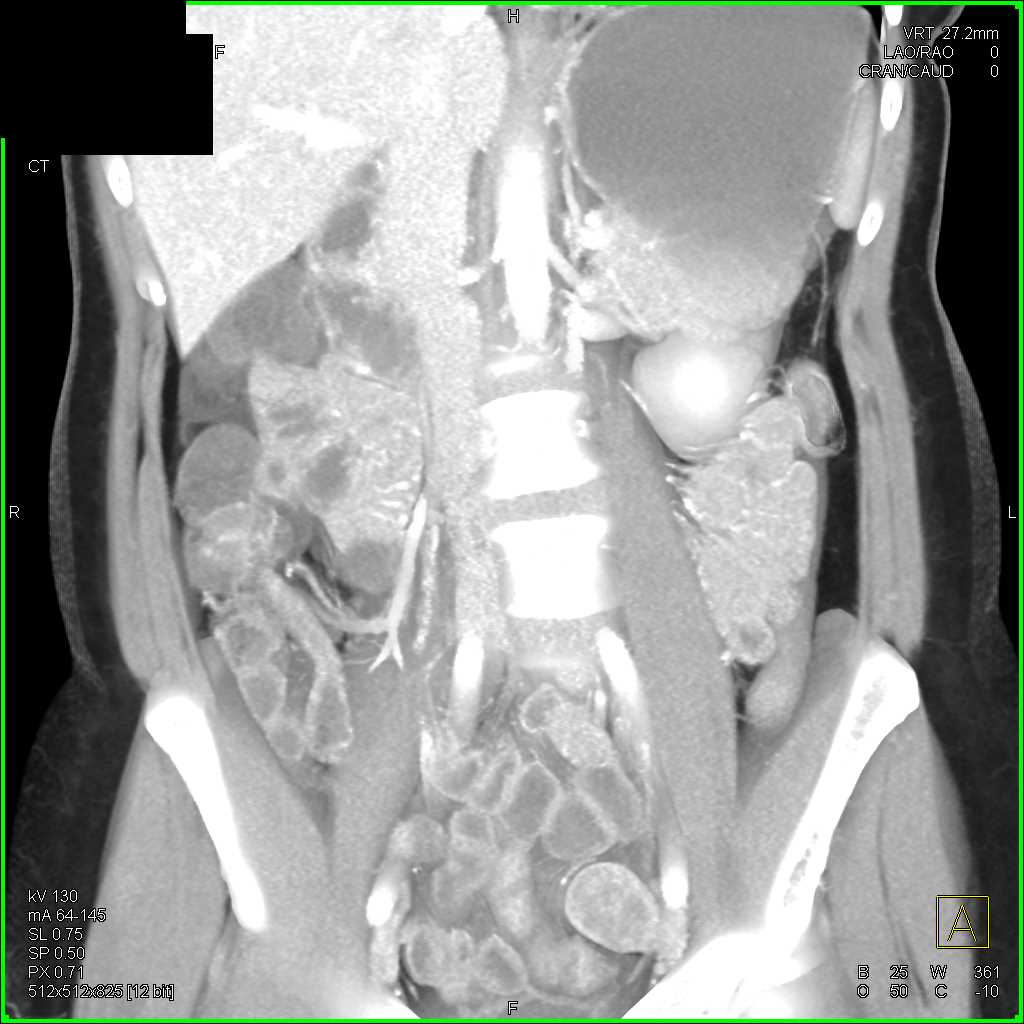

Crohns Disease Terminal Ileum